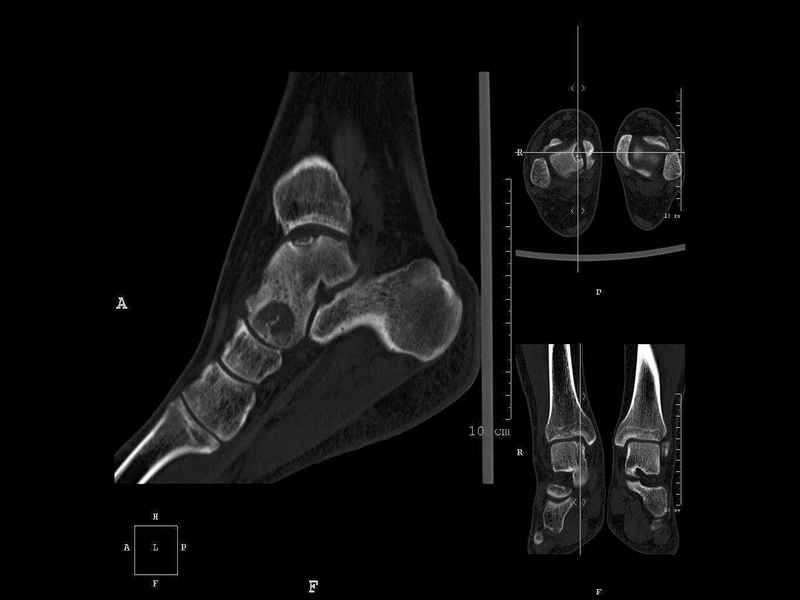

На СКТ картина рассекающего остеохондрита блока

таранной кости, киста шейки таранной кости с признаками импрессии суставной поверхности. А

также - разрастания переднего края б\берцовой кости сопровождающиеся клиникой импиджмент

синдрома.